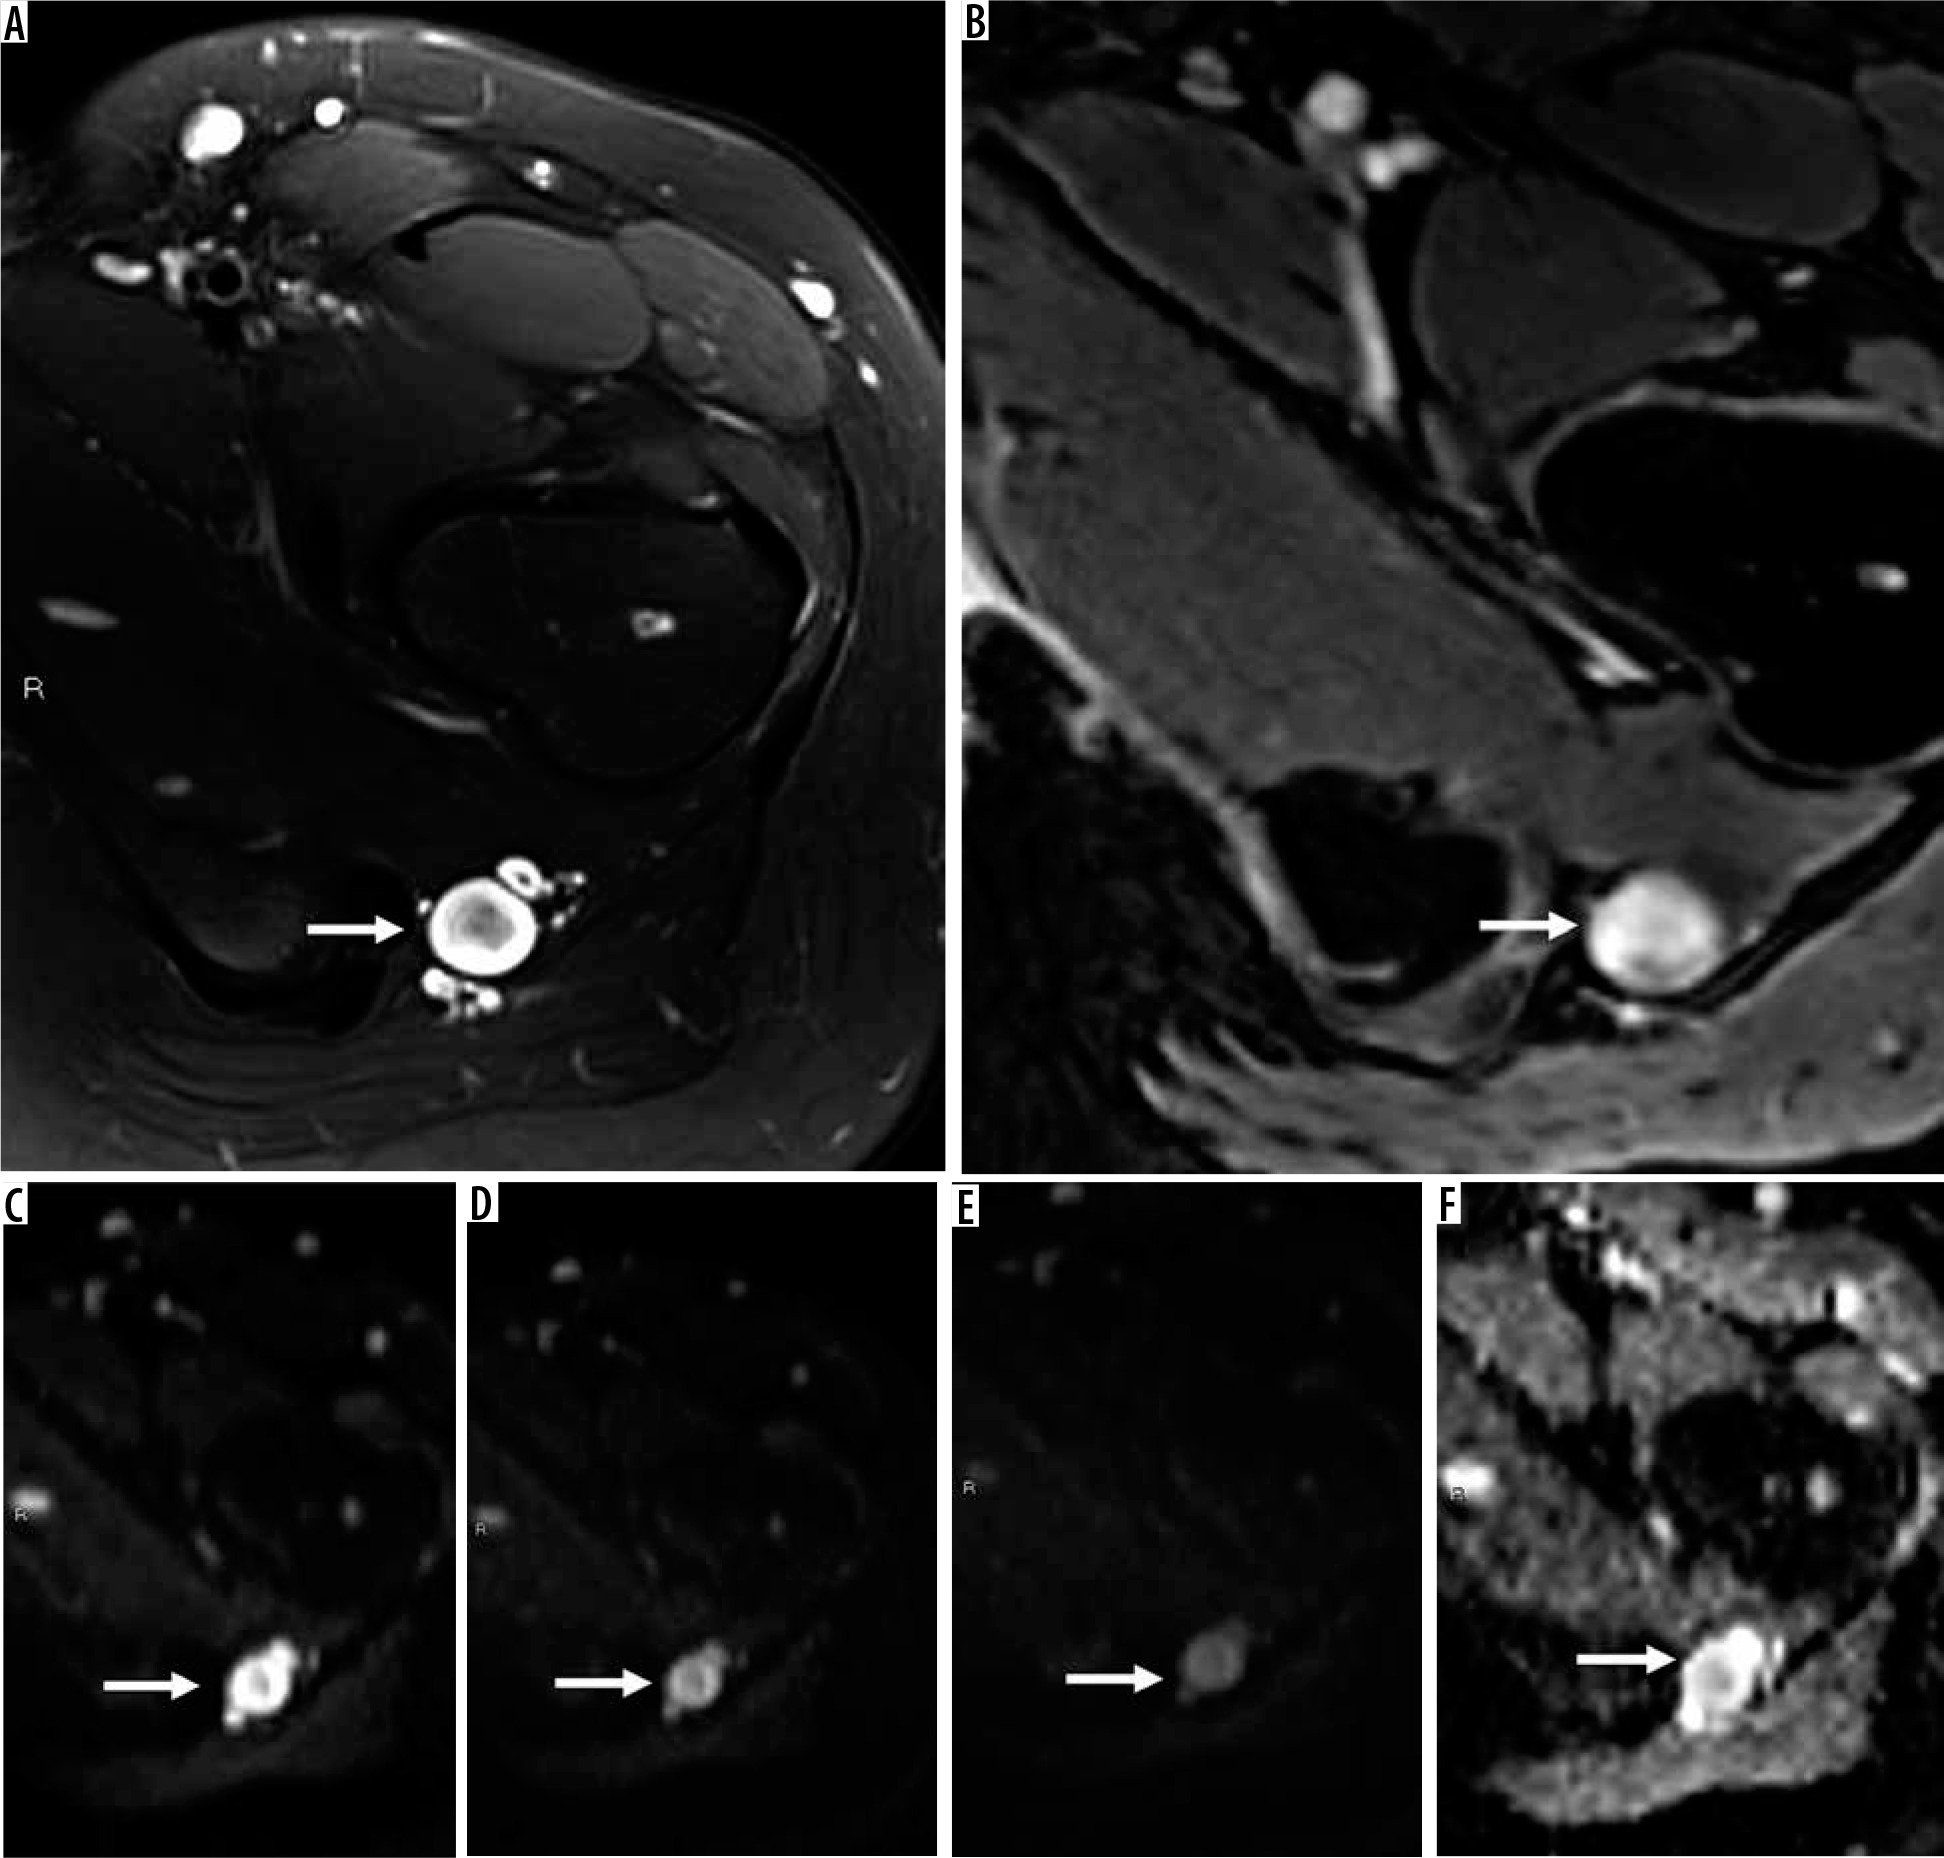

Figure 8

16-year-old girl with neurofibroma. Axial T2-weighted fat-suppressed (A) and T1-weighted fat-suppressed post-contrast (B) magnetic resonance( MR) images through the left proximal thigh show a small enhancing soft tissue mass along the sciatic nerve (arrows) with a target sign seen in (A). DWI using low b-value of 50 s/mm2 (C), intermediate b-value of 400 s/mm2 (D), high b-value of 800 s/mm2 (E), and lastly the ADC map (F) (arrows) show a soft tissue mass with a target sign: suggesting preserved zonal histological architecture of a peripheral nerve sheath tumours (PNST). A morphological target sign can be visible on fluid-sensitive and contrast-enhanced MRI sequences and indicates a benign PNST. The qualitative presence of target sign is more often seen on DWI using high b-values and ADC mapping based on the intrinsic T2 properties of a PNST when compared with routine MRI sequences, and suggests the preservation of the PNST’s internal histological architecture. Mean PNST diameter (> 4.2 cm) and minimum ADC values (≤ 1.0 × 10-3 mm2/s) have been found to accurate quantitative metrics that can be used to distinguish malignant PNSTs from benign PNSTs